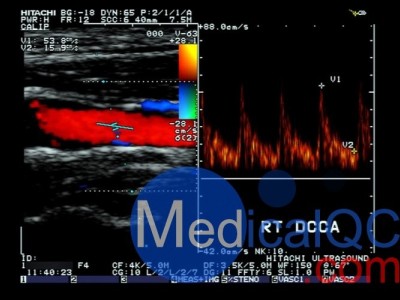

CIRS 043多普勒模体准确地模拟16个生理和测试波形。

CIRS 043多普勒模体“Mark 4”Doppler Phantom是使用多普勒超声的人员必不可少的工具。晶体控制电机使用先进的字符串目标技术精确地产生十六个预编程的波形。由于速度每秒调整1000次,因此您知道它是精确的和可重复的。

CIRS 043多普勒模体可以设置为使用水或速度校正液。如果您使用的是水,则会相应地调整琴弦速度,因此水中声音的不同速度不会影响您的测试。不像流体流动模体,目标不会改变; 你知道你的测试结果应该是每一次。

脉冲波形:16个预先编程和可选客户指定

包括波形:成人颈总动脉,颈动脉狭窄,股动脉,主动脉。胎儿大脑中动脉,肾动脉,脐动脉。小儿降胸动脉,动脉导管未闭。

测试波形:峰值速度为100,150和200厘米/秒的正弦波。三角波峰值速度为100,150和200厘米/秒。停止在0,20,40,60,80和100厘米/秒的阶梯波。